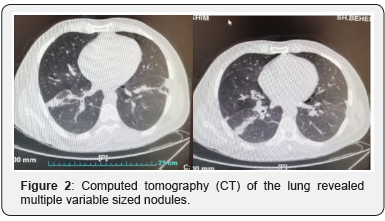

Chest radiography did show bilateral flatting and elevation of the diaphragms and significant hypo inflation as demonstrated by visualization of 6 posterior ribs. The radiographs demonstrate left lower lobe atelectasis (Figure 1). Ultrasound of the abdomen showed slight enlargement of kidneys (right kidney 135 mm, left kidney 140 mm). Computed tomography (CT) of the lung revealed multiple variable sized nodules (Figure 2). Spiral CT scan of abdominopelvic with IV and oral contrast noted intraluminal defect in right renal vein and IVC in favor of thrombosis (Figure 3). The abdominal aorta and its branches in particular renal arteries appear normal in contrast abdominal CT angiography but inferior vena cava (IVC) right renal artery revealed filling defect can be a suggestion for RVT. A contrast-enhanced CT angiography of pulmonary artery revealed multifocal intraluminal filling defects in most of both lower lobe segmental and subsegmental branches, that favor of thromboembolism (Figure 4).